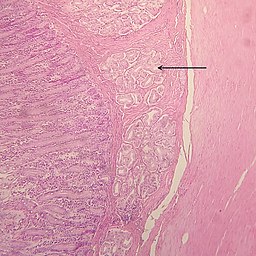

Histología de las glándulas de Brunner

Las glándulas de Brunner son especialmente abundantes en la mucosa y la submucosa que se encuentra rodeando la musculatura duodenal en el intestino delgado.

Tienen forma tubular y se ramifican de una forma muy comprimida a lo largo de los epitelios del duodeno y el yeyuno. Todas las células de estas glándulas tienen la forma típica de los ácinos glandulares.

Las células de estas glándulas están especializadas en la secreción de sustancias, tienen forma de ductos agrupados en cúmulos arboriformes que terminan en poros especializados para la secreción.